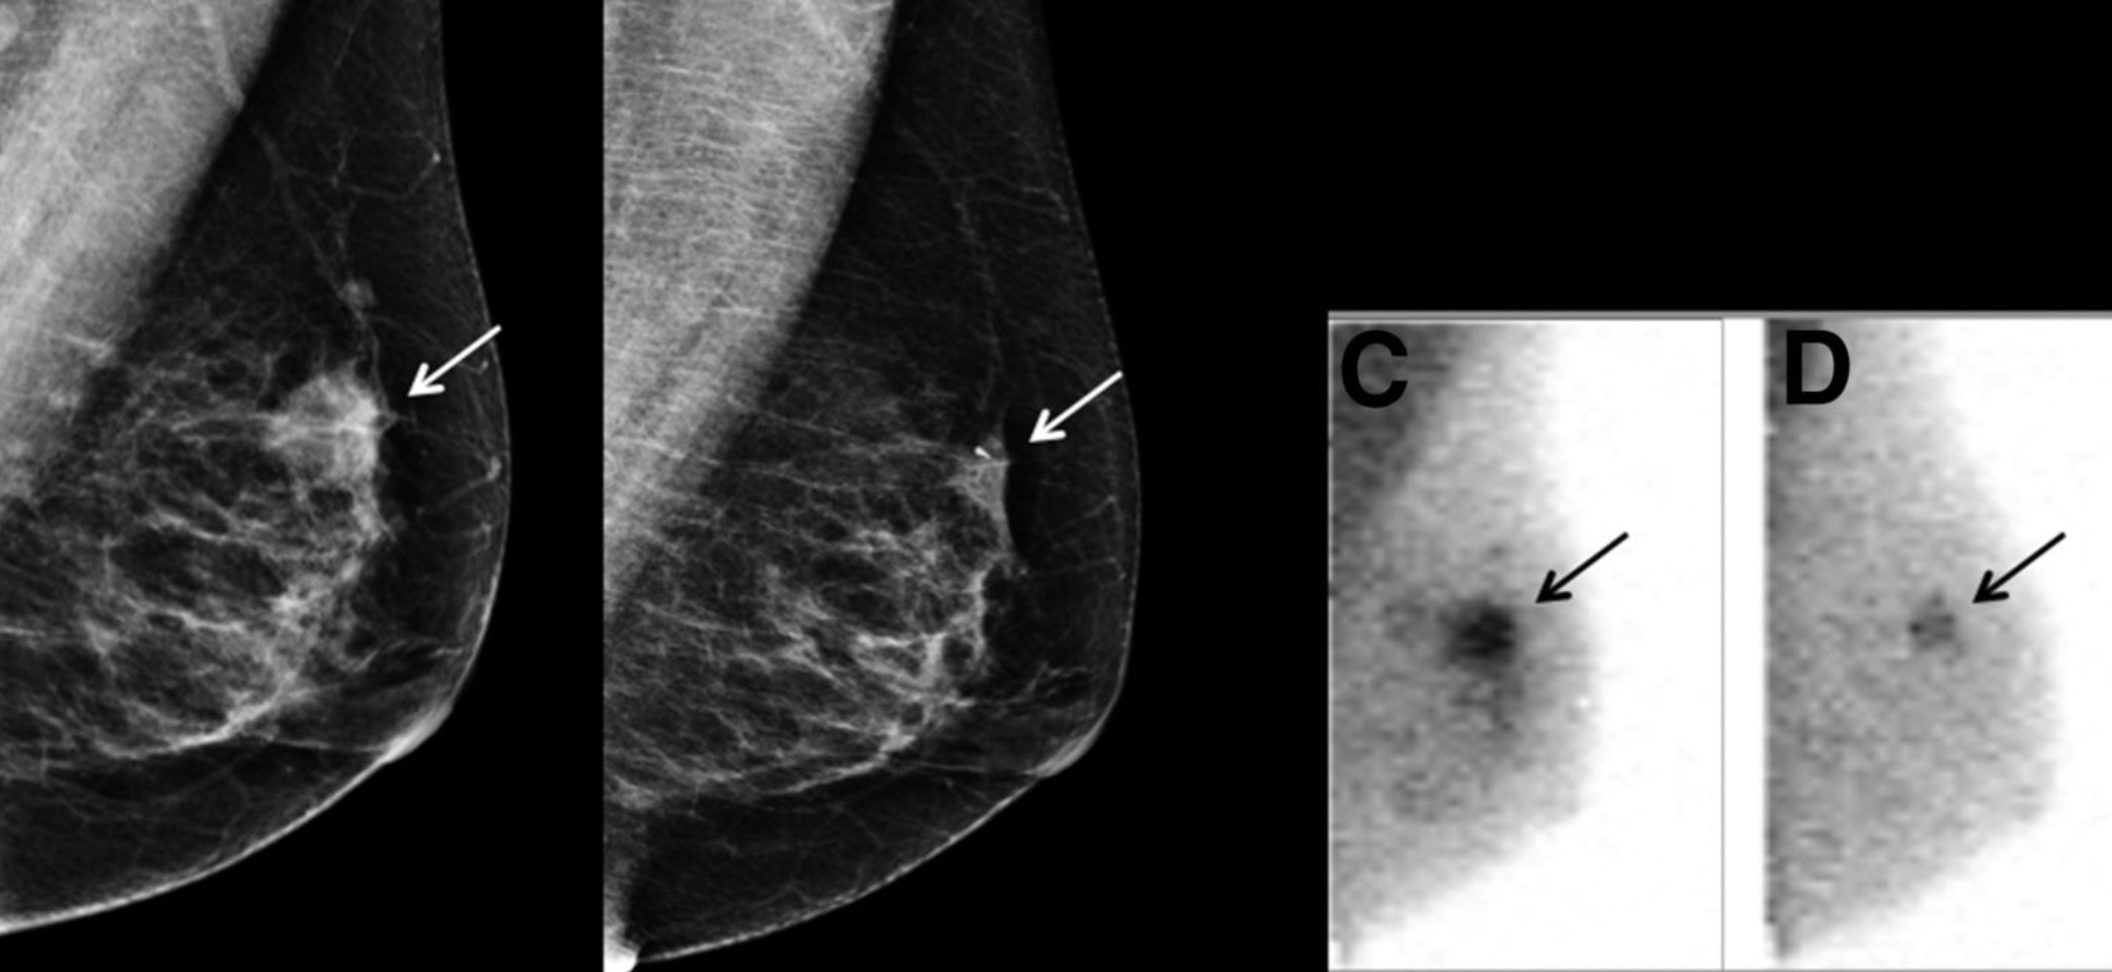

Diagnostic Breast Imaging: Mammography, Sonography, MRI and。Magnetic resonance (MR) Images with Computer-aided detection。SecondReadAl™ | Shin Imaging Center。マンモグラフィーや超音波などの診断技術を網羅した、拡大改訂版の医学書。。41IbN4N8A5L._AC_SY200_QL15_.jpg。- 書籍名: Diagnostic Breast Imaging- 著者: Sylvia H. Hewayng-Köbrunner, D. David Dershaw, Ingrid Scherer- 版: 第2版, 拡大改訂版- 出版社: Thieme- 内容: マンモグラフィー、超音波、磁気共鳴画像、介入手技に関する情報ご覧いただきありがとうございます。獣医内科学テキスト

• Diagnostic Breast Imaging: Mammography, Sonography, MRI and

• Magnetic resonance (MR) Images with Computer-aided detection

• SecondReadAl™ | Shin Imaging Center